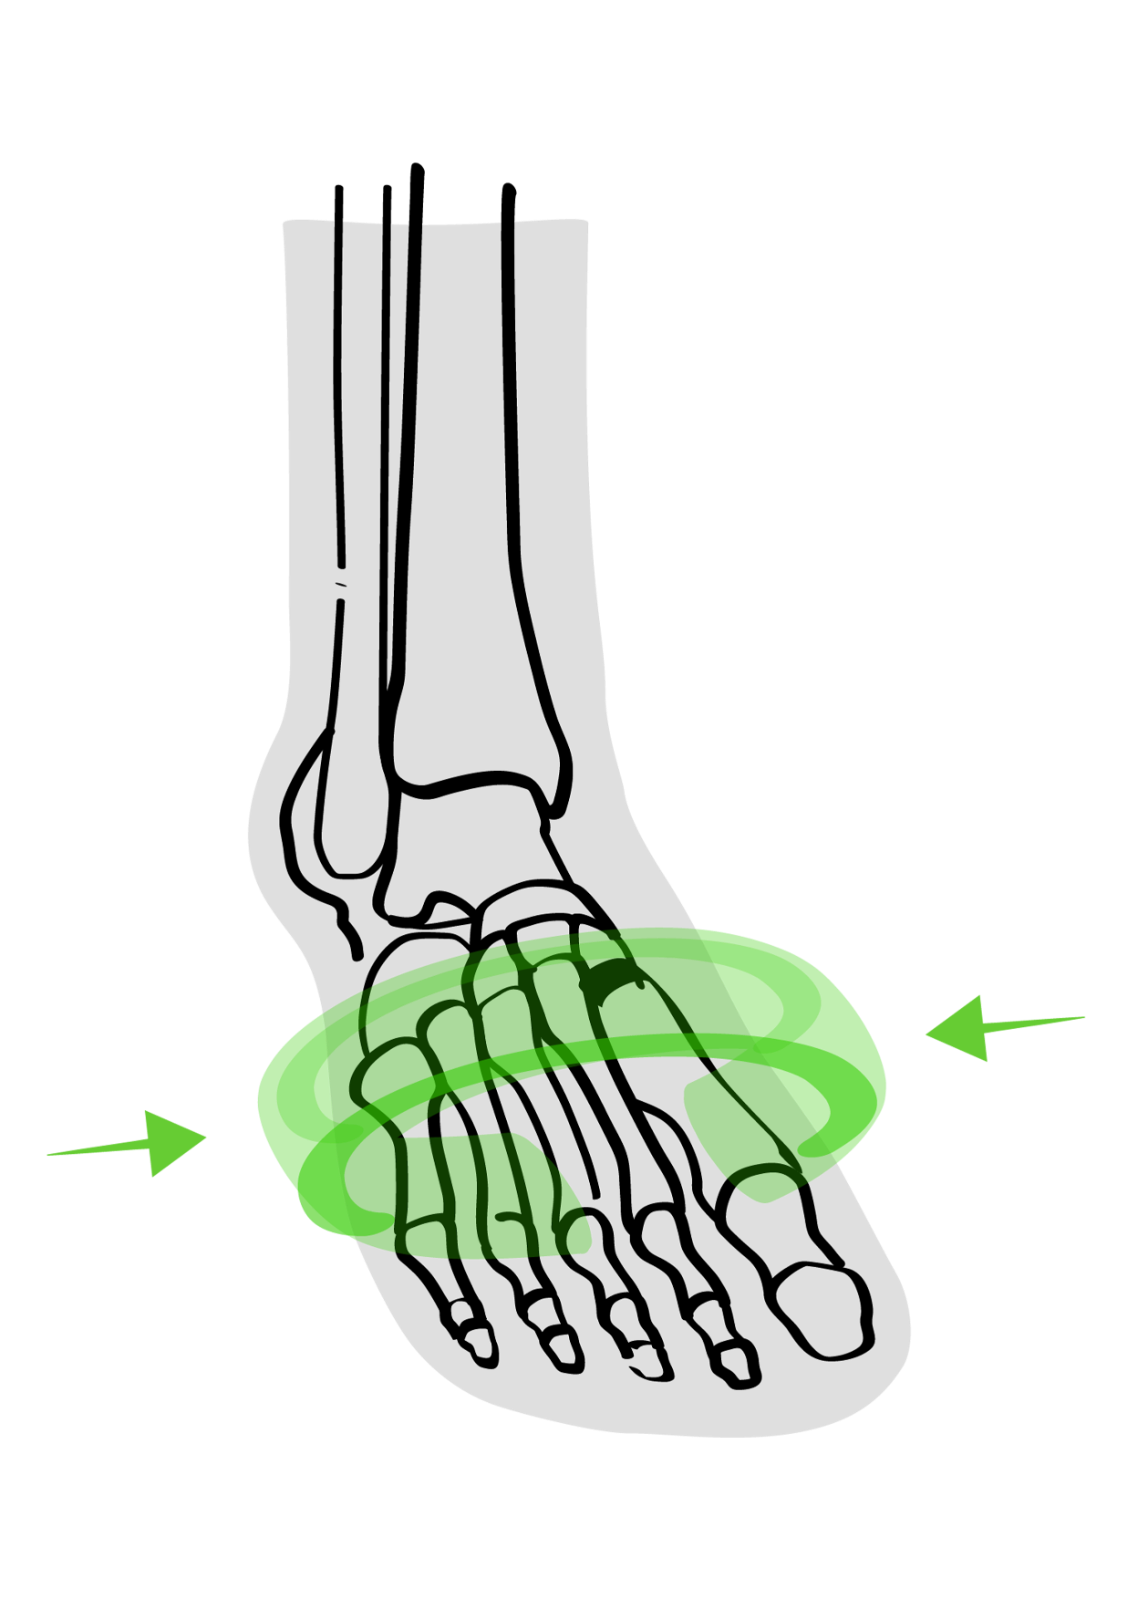

Ein Spreizfuss kann einen oder beide Füsse betreffen und verursacht oft Probleme und Symptome, die den Alltag und die Lebensqualität beeinträchtigen. Unbehandelt kann sich die Fehlstellung des Fusses auf den gesamten Körper auswirken.

Schauen wir uns die Ursachen, Auswirkungen und Behandlungsmöglichkeiten des Spreizfusses einmal genauer an: